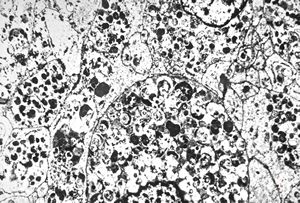

F, 24y. | molluscum contagiosum … virions

F, 24y. | molluscum contagiosum

F, 24y. | molluscum contagiosum